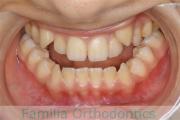

下の前歯が後ろにあるのが気になるとのことで来院されました。非抜歯で行うことも可能でしたが、上下左右から小臼歯抜歯をして治療を行うことをご希望になりました。

マルチブラケット法にて治療を行い、約3年、40回の通院が要でした。

かみ合わせが深い(上の前歯で下の前歯が覆われてしまう)ので、保定をしっかりしないと、また深くなってきてしまいやすいです。

前歯の関係など